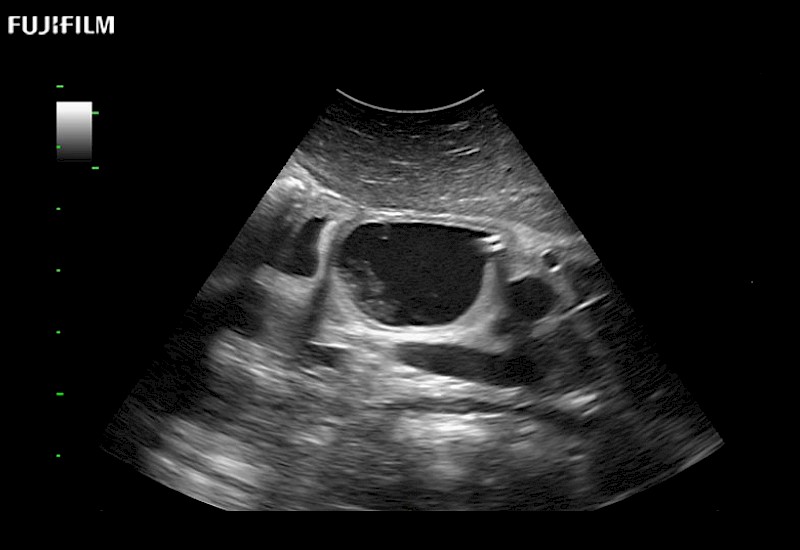

Learn moreFujifilm Healthcare continues to listen to the experts, our neurosurgeons, by developing an ultrasound system specifically designed for the Operating Room.

Guidance is the fundamental purpose for all of our surgical ultrasound technology. Fujifilm Healthcare is committed to designing tools that help neurosurgeons navigate inside the human body and provide the necessary information to immediately make critical surgical decisions.

With the ARIETTA Precision the next level of surgical ultrasound is here.